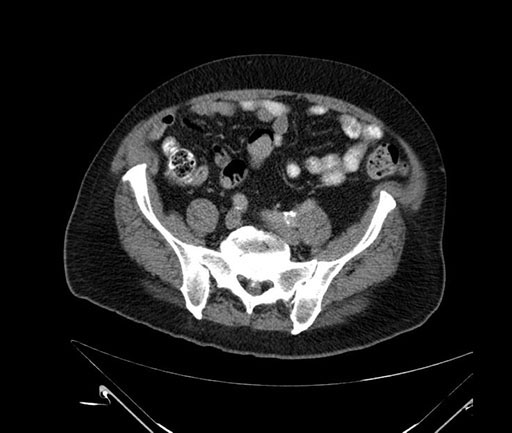

Axial - stented